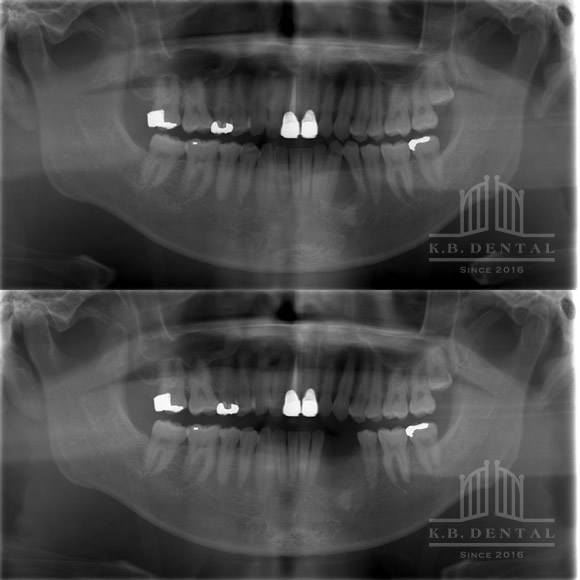

術後2年経過の最も典型的なエナメル上皮種です。再発率が非常に高いので最低でも5年以上の経過観察が必要となります。今回は摘出術と一部健常域まで辺縁切除(骨を削る)を行いました。

1枚目(パノラマ)上:術前 下:術後 摘出部分に新生骨を認めます。